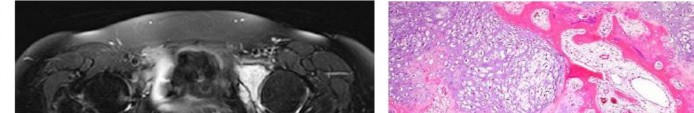

Question 17

A 35-year-old female is diagnosed with a locally aggressive giant cell tumor of the distal radius. Preoperative administration of Denosumab is planned to facilitate downstaging and joint-salvage surgery. What is the exact mechanism of action of Denosumab in this context?

Explanation

Denosumab is a fully human monoclonal antibody that specifically binds to RANKL (Receptor Activator of Nuclear factor Kappa-B Ligand). By binding to RANKL, it prevents it from interacting with the RANK receptor on the surface of osteoclasts and osteoclast precursors. In Giant Cell Tumor of bone, the neoplastic mononuclear stromal cells express high levels of RANKL, which aggressively recruits and activates the reactive multinucleated giant cells (osteoclasts) that cause bone destruction.